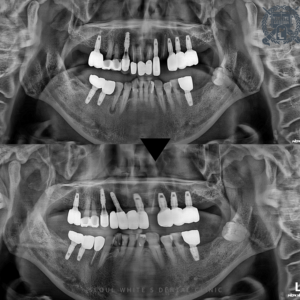

26.02.02

아래 임플란트와 신경치료, 보존치료가 마무리된 모습입니다. 환자분의 경우, 치료가 필요한 치아가 많았지만 아래를 먼저 마무리 한 상태에도 너무 편안하게 식사를 하시게 되었고, 통증이 사라져서 일상이 많이 편안해지셨다고 하셨어요!

단, 아직 상악 치아들 치료가 남아있으며 환자분께서 아직 구강관리가 어려우셔서 부러진 치아들도 발생하여 서울화이트S치과는 모든 치료가 온전히 마무리 될 때까지 책임지고 진행해 드릴 것을 약속드렸습니다.